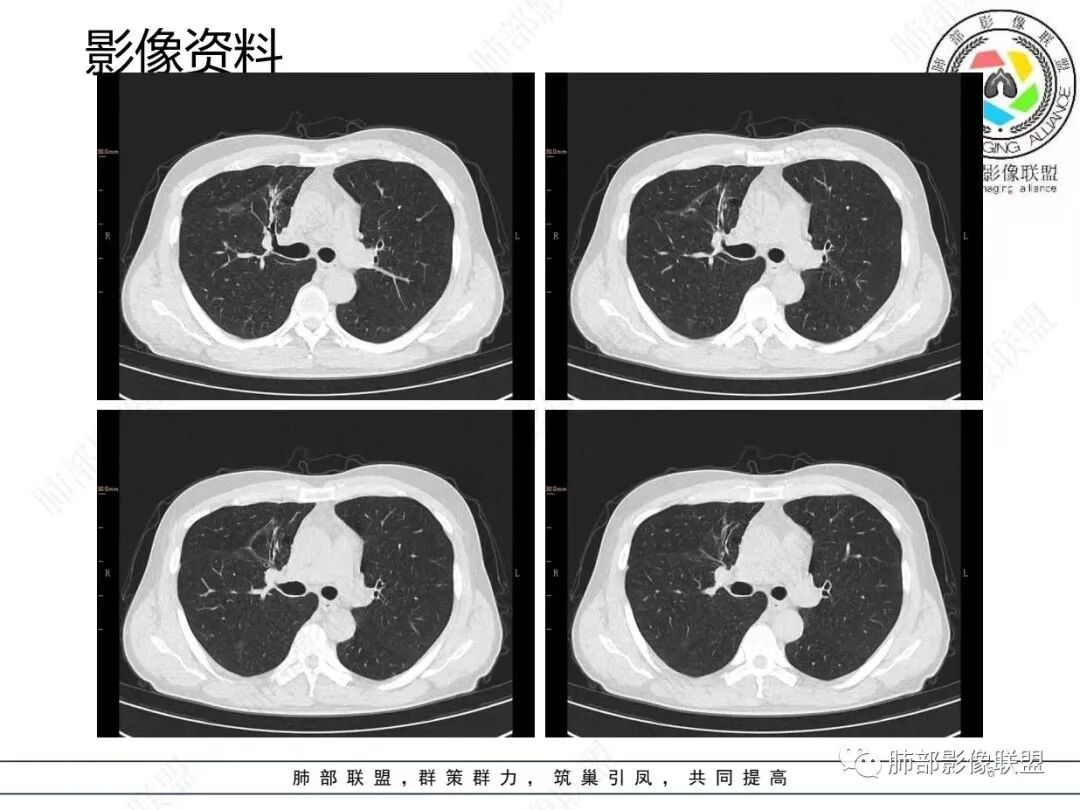

1.临床特点:52岁男性,体检发现肺结节。有吸烟史。非小细胞肺癌相关抗原与神经元烯醇化酶轻度升高。2.影像特点:右肺上叶前段可见不规则结节影,整体膨隆,可见浅分叶,周围局部可见边界清楚的磨玻璃影。可见血管集束征及脐凹征,临近叶间胸膜受牵拉凹陷,局部支气管到达病灶边缘后显示截断。3.病例小结:中老年吸烟男性,右肺上叶前段不规则结节,膨胀感较明显,收缩力强,支气管截断,加上边界清楚的磨玻璃影。符合浸润性腺癌表现。

4.相关知识:浸润性肺腺癌分为:附壁状、腺泡状、乳头状、微乳头状、实体型,较少见的生长模式包括浸润性黏液型、胶样、肠型和胎儿型。腺癌影像表现为磨玻璃影、部分实性结节、实性结节或实变。